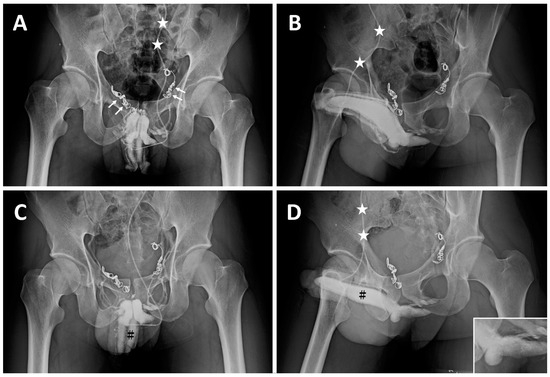

| ED a | 2008 | Early detumescence of rigid erection, position-dependent | A multiplanar diagnosis workup showed a veno-occlusive dysfunction. |

| CE(I) b | 2010 | Same | Acute chest pain was caused by the migration of a dumbbell-shaped coil to the right pulmonary artery. |

| CE(II) c | November 2012 | Same | A tapeworm-shaped coil was noted in the region of the right iliac vein at 90 degrees to the venous channel. |

| CE(III) d | May 2014 | Same | A pigtail-shaped coil was shown at the left internal pudendal vein level at 90 degrees to the venous channel. |